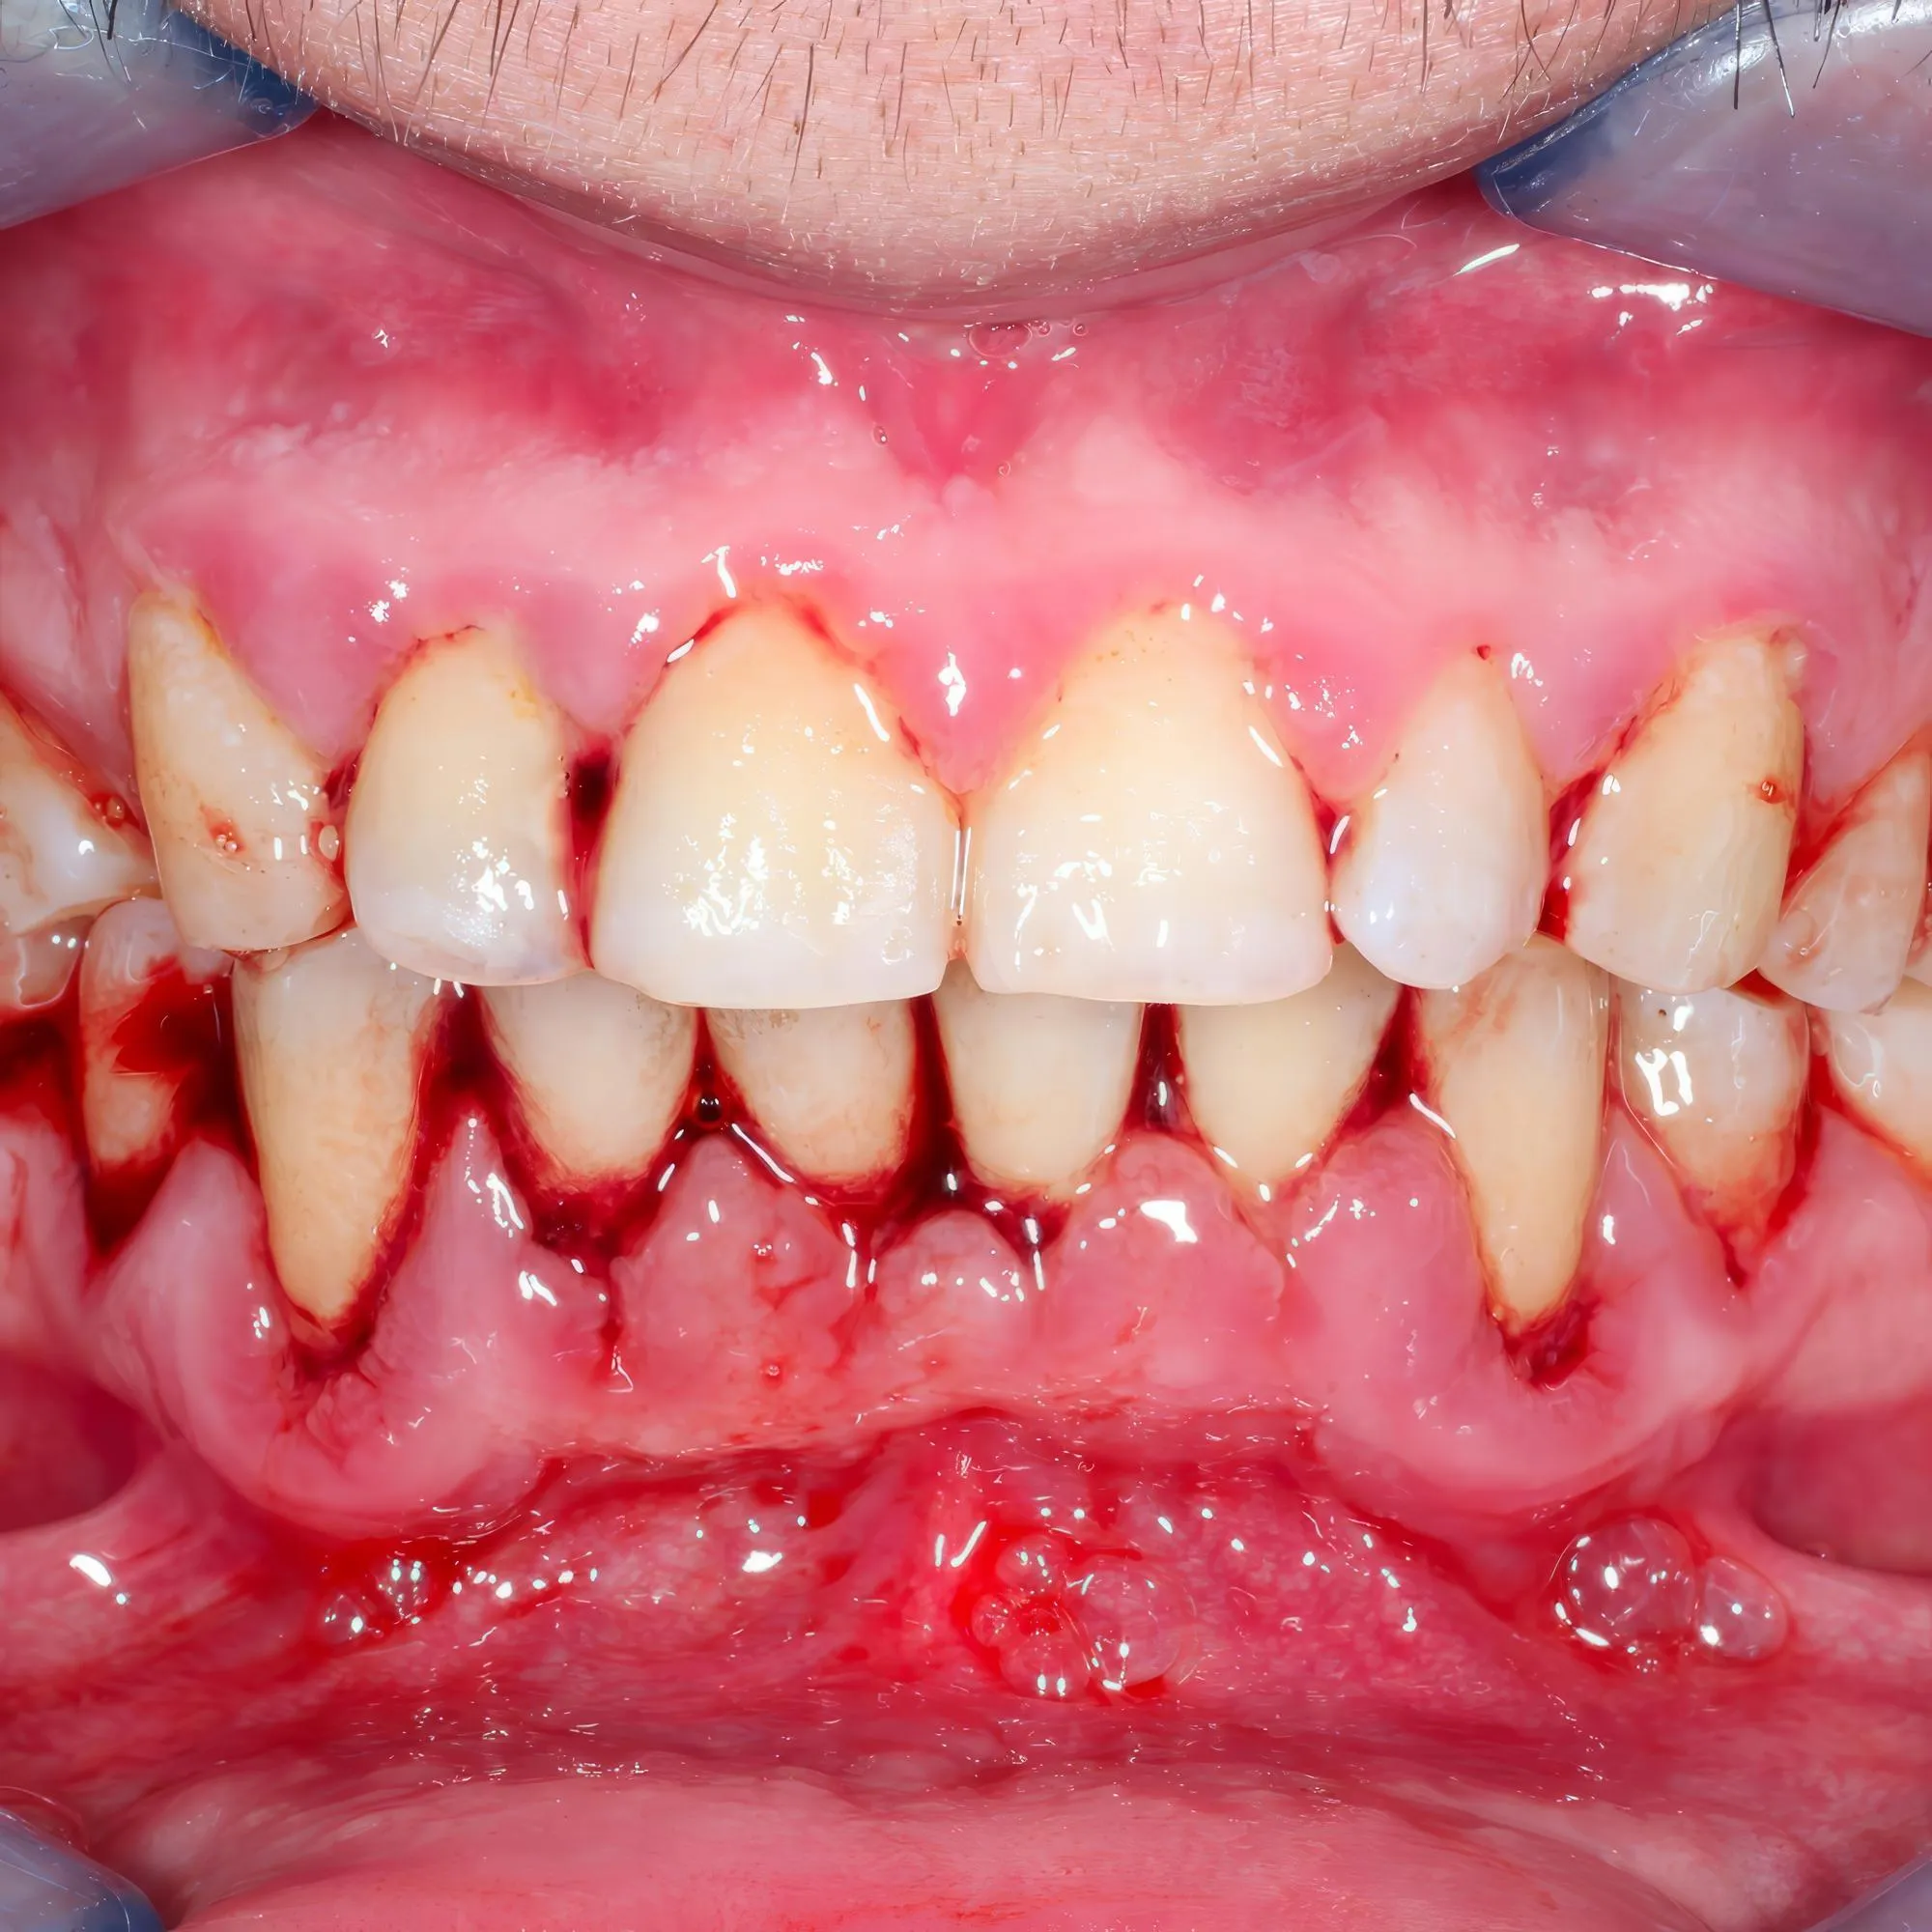

When non-surgical doesn’t do the job, surgery becomes the hero.

• Flap Surgery: Lift gums, clean deeply, place back neatly.

• Gum Grafting: Fixes receding gums using tissue from your mouth.

• Bone Grafting: Adds bone where it’s lost.

• Guided Tissue Regeneration: Adds bone where it’s lost.

Sure, sounds fancy. But these are standard procedures. Doctors in Dwarka do them every day. Your smile’s in safe hands.